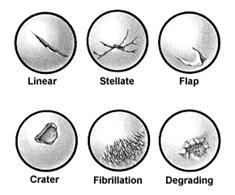

Another classification system has been devised by Bauer and Jackson who identified six types of lesions of the articular cartilage. In their series, they found that rotational forces in direct trauma were the most common causes of injury to the articular cartilage. In most of their cases, the lesions were in the weight-bearing area of the articular cartilage, usually in the medial compartment. The most common associated lesion was a tear of the meniscus. The six types of changes are linear crack, stellate fracture, flap, crater, fibrillation, and degrading (Fig. 29-58). The linear crack is usually split-thickness, and it is often encountered on the lateral tibial plateau in association with ACL injuries. Stellate fracture is usually of a diverging type with central flaking of the cartilage. This is the most common type identified in the series (Fig. 29-59). In a flap tear, the cartilage is avulsed from the subchondral bone (Fig. 29-60). The crater is usually full-thickness and subchondral bone is exposed. Fibrillation is of partial thickness and corresponds to the old Outerbridge classification type III. The final characteristic appearance of abnormal articular cartilage is degenerative and extends down to the subchondral bone.